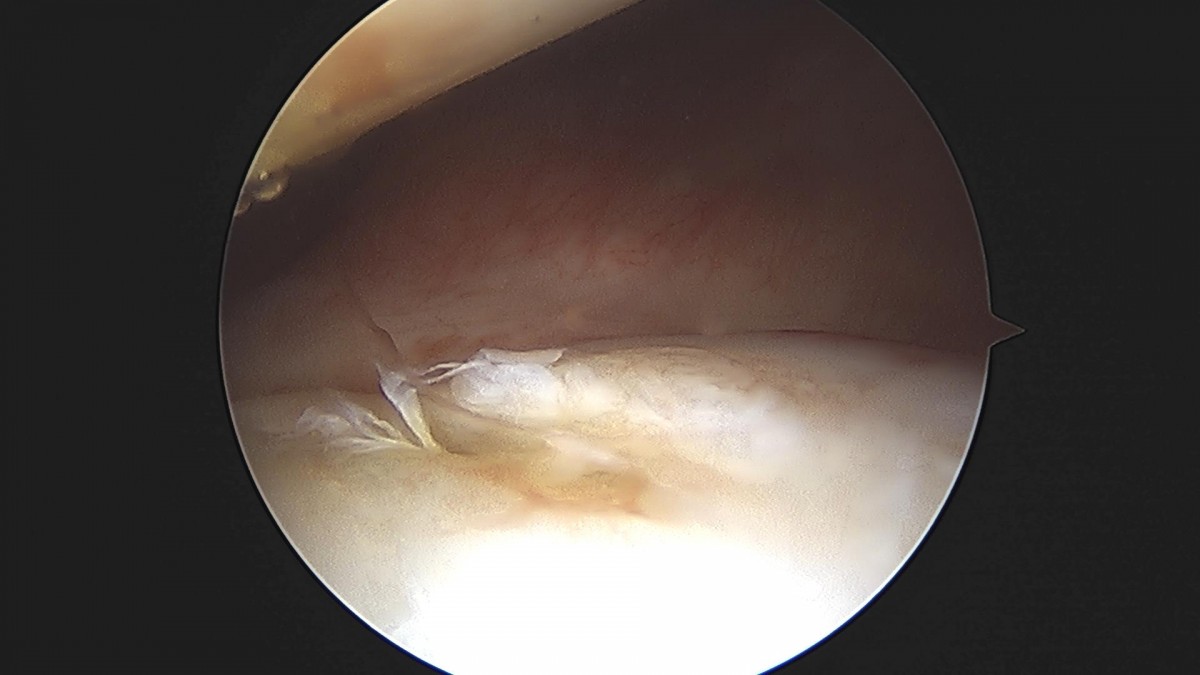

배우한원장님 어깨관절와순봉합술 (4315)유O 환자

작성자 최고관리자 댓글 0건 조회 1,291회 작성일 22-05-09 11:51